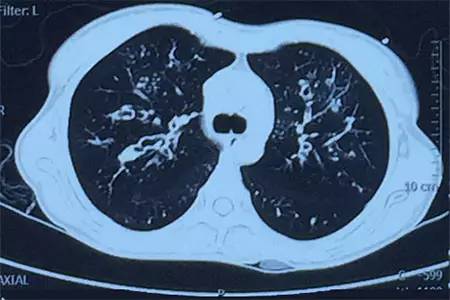

肺CT見下圖

該患者肺部影像學表現(xiàn)為明顯的支氣管擴張,同時伴有彌漫的滲出斑片影,考慮合并感染,細菌學培養(yǎng)提示為綠膿桿菌,結(jié)合藥敏結(jié)果給予頭孢他啶+阿米卡星抗感染,患者存在II型呼吸衰竭予氣管插管機械通氣支持,加強體位引流排痰,治療18天,患者情況好轉(zhuǎn)出院。